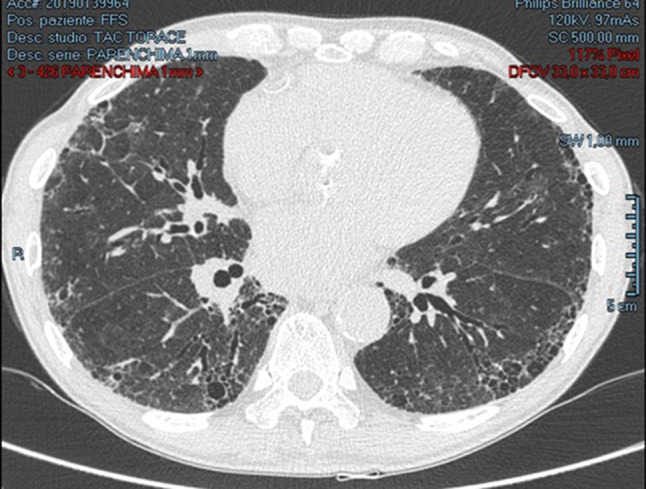

Therefore, we examined diaphragm motility by M mode through a sub-rib scan; a normal/high excursion compared to the reference standard during normal breath was evident [7], but a reduced excursion with forced breathing was present. (Fig. 1).

Fig. 1.

M-mode examination revealed a normal/high diaphragmatic excursion during resting breathing, while there was a reduced excursion during forced inspiration